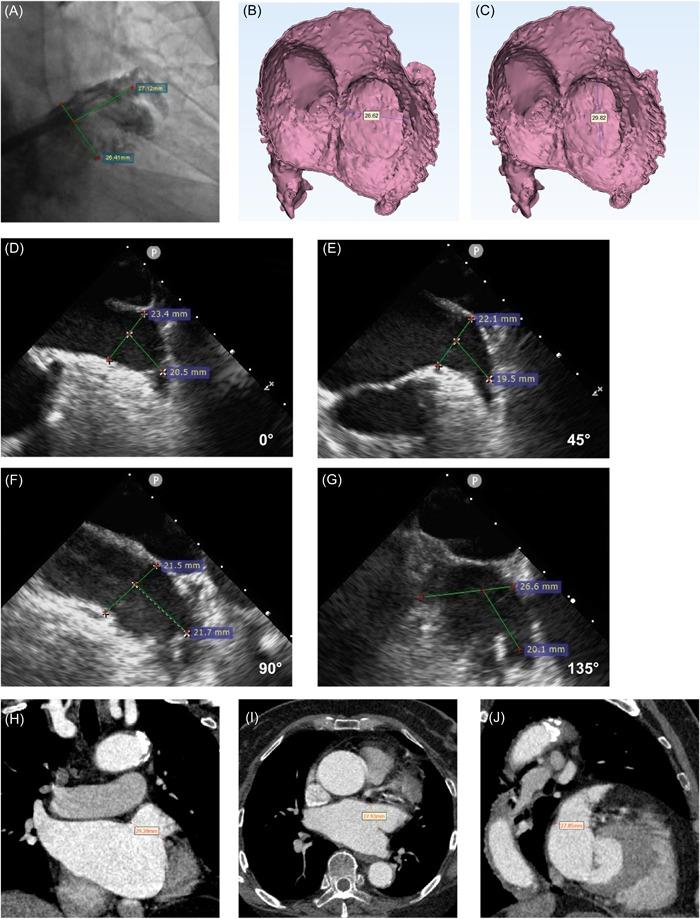

We aimed to study the accuracy of left atrial computed tomography angiography (CTA), three-dimensional (3D) reconstruction using CTA, two-dimensional transesophageal echocardiography (2D-TEE), and digital subtraction angiography (DSA) for measuring the diameter of the LAA and compare their value for selecting occluder size.

We retrospectively evaluated data for 148 patients with nonvalvular atrial fibrillation who underwent successful LAAC. CTA and 2D-TEE of the left atrium and pulmonary vein were performed before LAAC. We performed 3D reconstruction of the left atrium and LAA using Mimics and 3-matics software. DSA of the LAA was performed during surgery.

Values measured via CTA 3D reconstruction were significantly higher than those measured using other methods. DSA-measured values were significantly lower than those measured via CTA and CTA 3D reconstruction. Occluder size was positively correlated with LAA orifice diameter. The differences between occluder size and DSA, 2D-TEE, CTA, CTA 3D reconstruction measurements were 4.96 ± 2.58, 4.64 ± 2.50, 4.04 ± 1.37, and 2.92 ± 1.38 mm, respectively. Intraclass correlation coefficients for these methods were -.067, .006, .241, and .519, respectively.

CTA 3D reconstruction provides the best correlation and consistency between the measured LAA orifice diameter and occluder size. Adding 2-4 mm to the maximum LAA orifice diameter based on 3D-CTA may aid in selecting the appropriate WATCHMAN device.